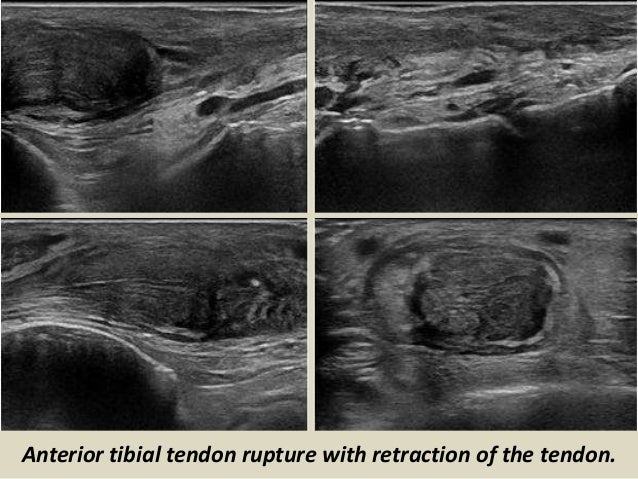

37. 37. Anterior tibial tendon rupture with retraction of the tendon.

33. 33. ANTERIOR COMPARTMENT The tendons of the anterior ankle, compared with the rest of the ankle tendons are rarely affected by disease. The anterior tibial tendon is the most prone to abnormalities, like tendinopathy, tenosynovitis and its place between the most frequent rupture is extensor retinaculum and insertion into the first cuneiform and the base of the first metatarsal. Sometimes the retracted tendon stump causes a nodule on the anteromedial aspect of the distal portion of the leg, making clinically confused with a tumour or cyst.

Anterior tibial tendon rupture with retraction of the tendon.